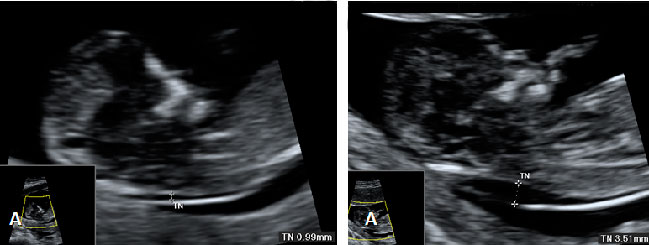

Ecografía Embarazo 2D y 3D Semana 12 - PLIEGUE NUCAL